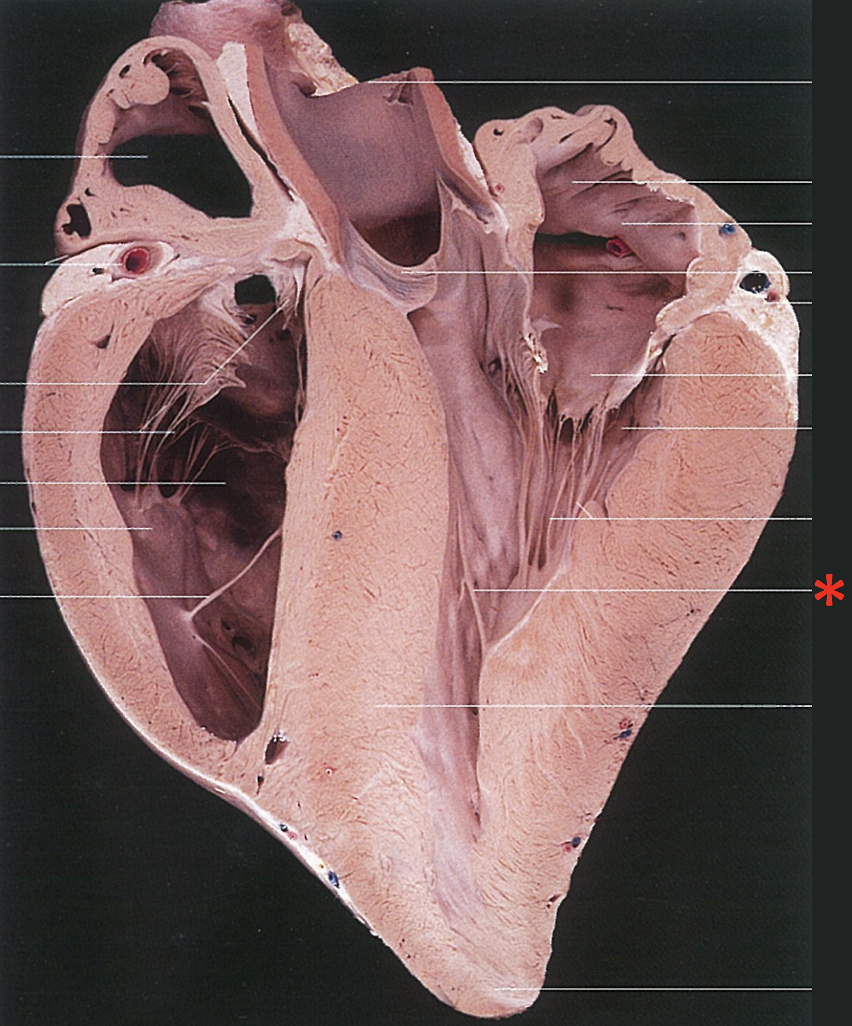

Is this a left or right type heart?

Right-Type

[Equine]